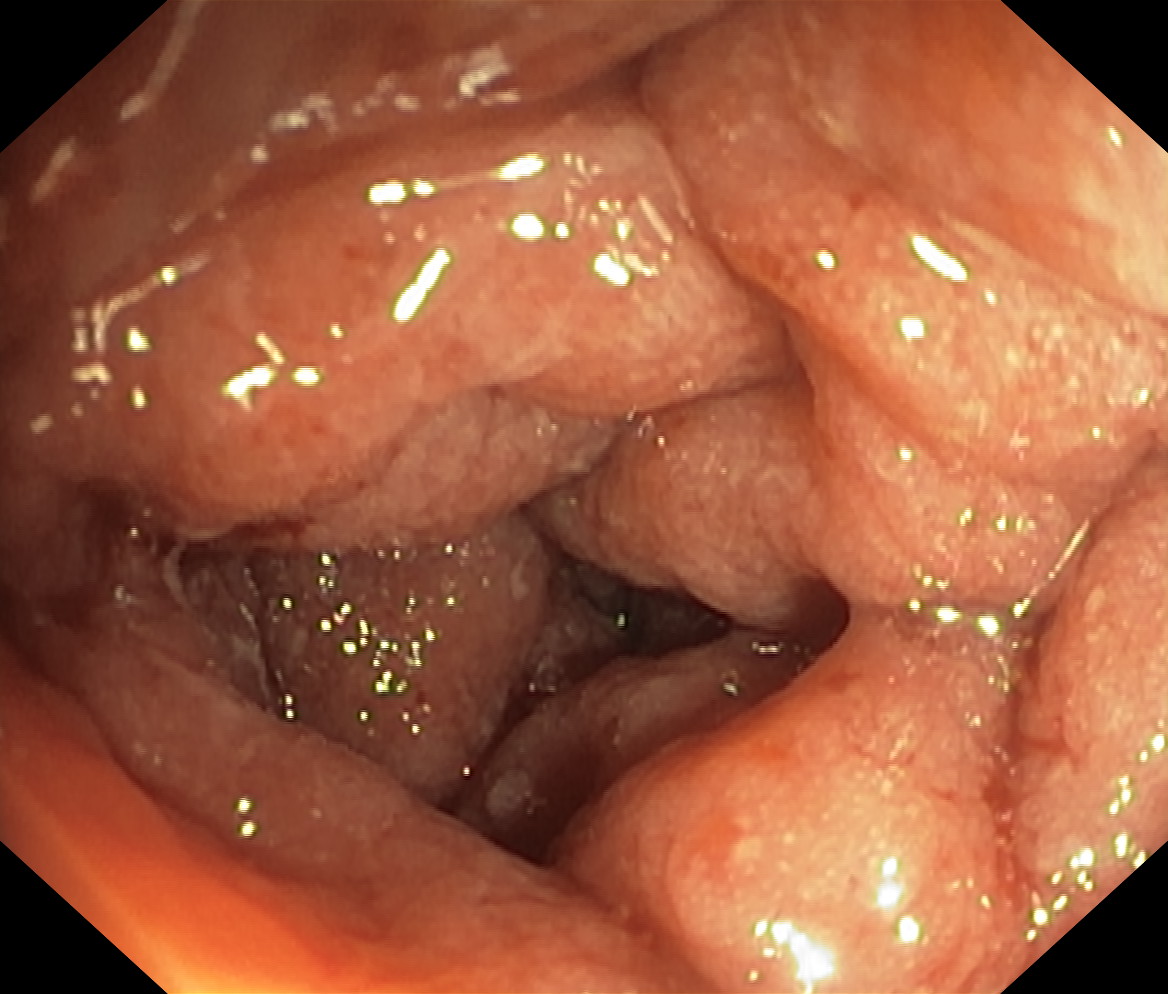

Zapalenie wrzodziejące jelita grubego